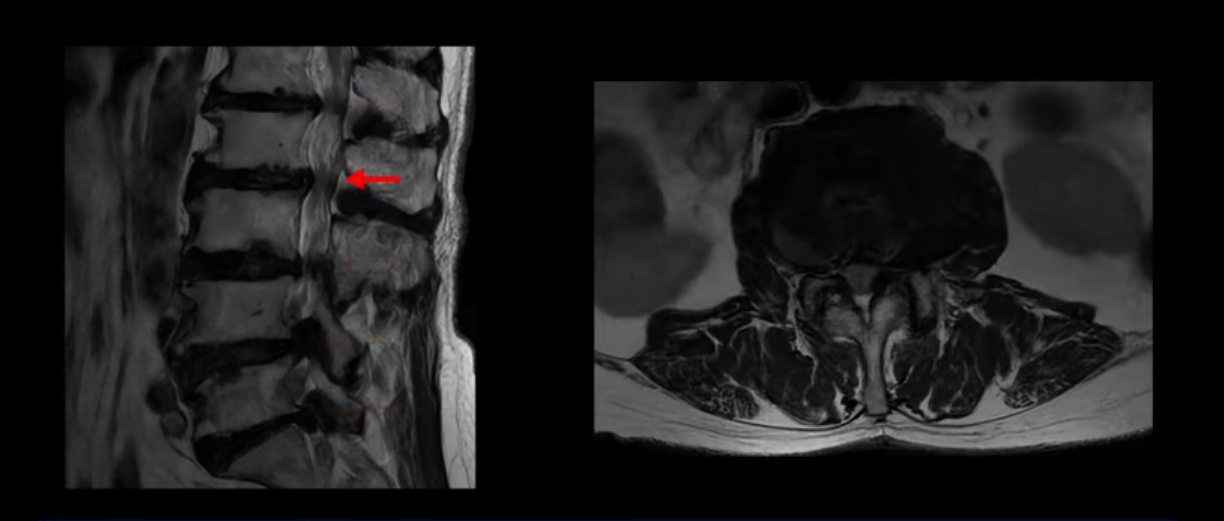

MRI 보시면 (2-8) 허리의 5마디가 전부 다 심하게 퇴행되어 있습니다.

5마디 전부 다 심한 중심성 협착이 있습니다.

이렇게 모두 다 심하게 막히는 경우는 드문데요. 또한 오른쪽, 왼쪽 신경이 빠져나가는 추간공도 다 심하게 막혀있습니다.

오른쪽, 왼쪽 이렇게 신경 구멍들이 다 좁아지고 신경이 눌리니까 양쪽 다리가 발바닥까지 아파서 걷기 어렵고 양쪽 발이 10년 넘게 시린 겁니다. 당연히 수술해서 눌린 신경을 풀어줘야 한다고 들으셨는데요. 이런 환자분을 어떻게 수술 없이 치료할까요? 지금부터 설명해 드립니다.

이분 신경이 눌리는 증상은 오래됐지만, 증상이 아주 심해진 건 올해 들어와서입니다. 그럼, 이분 MRI 영상도 이렇게 심하게 안 좋아진 게 올해 들어와서일까요? 이분의 MRI로 보이는 협착은 아주 오래된 겁니다. 그래서 신경 구멍이 심하게 좁아진 것도 올해가 아니고 오래된 겁니다. 작년, 재작년에 훨씬 덜 아팠을 때 MRI를 찍었어도 신경 구멍 좁은 정도는 별반 차이가 없었을 겁니다.

실제로 수많은 논문에서 70세 이후 MRI로 협착이 보여도 아프지 않은 무증상 협착이 많다고 설명합니다. 협착이 있어도 안 아픈 사람들이 많다는데, 이게 왜 그럴까요? 근육 기능이 정상적이고 좋은 사람들은 근육이 허리를 잘 지지해 주니까 협착이 있어도 신경이 덜 눌리거나 안 눌리는 겁니다. 즉 근육이 좋으면 신경이 덜 눌리고 근육이 좋아지면 협착증이 좋아지는 겁니다. 그래서 저희가 근육 재활치료를 통해 근육의 기능을 회복시키면서 동시에 신경의 기능을 회복시키는 치료를 하는 겁니다. 이런 분들이 근육 재활치료를 통해서 협착증 증상이 좋아진다면 이런 분들의 협착증도 아프지 않은 무증상 협착으로 바뀌게 되는 겁니다.